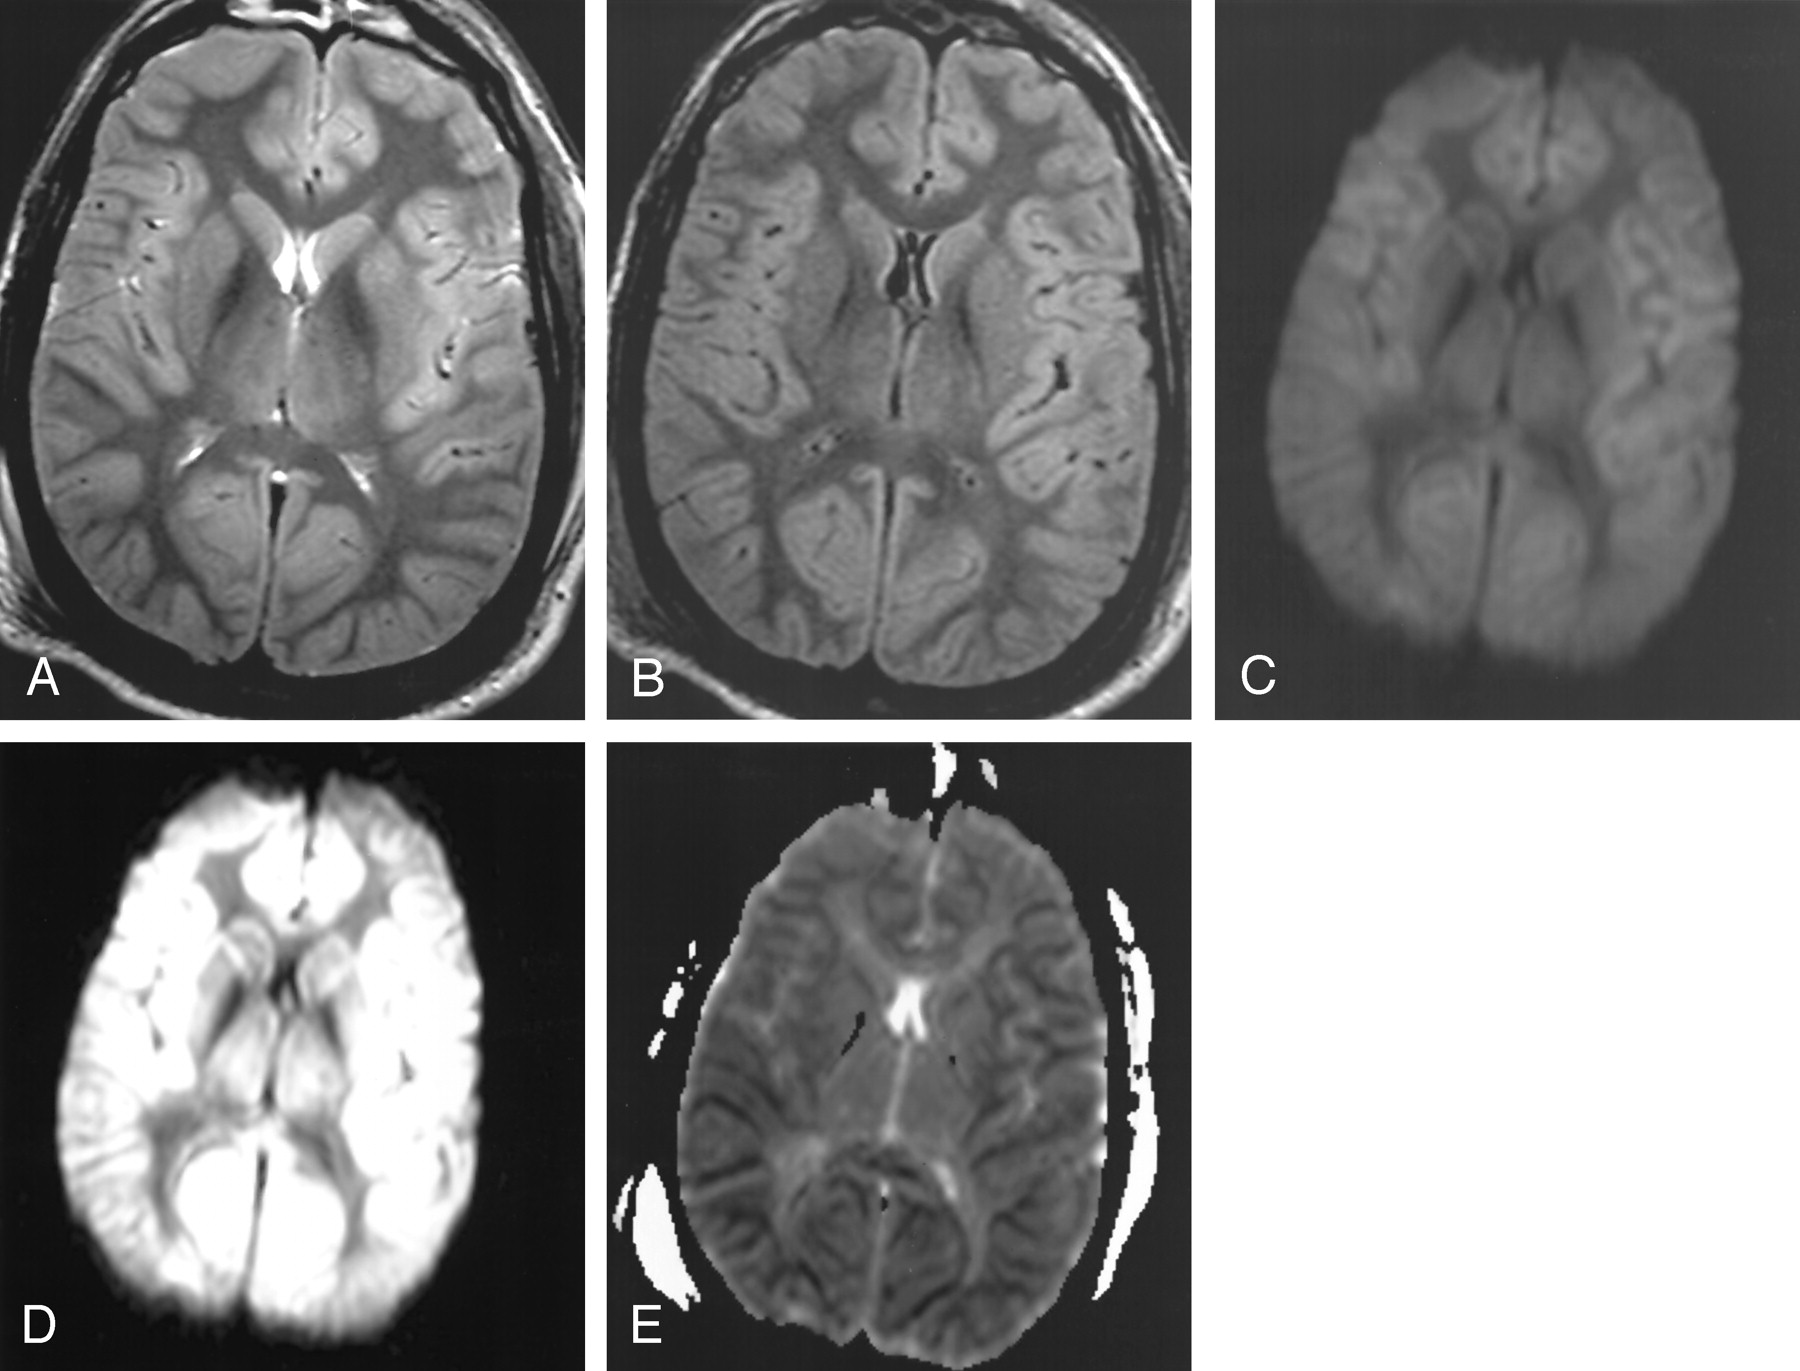

Figure 3 (patient 6) reflects the findings at MR imaging (performed with the 3T MR system) in a patient presenting after cardiac arrest; the initial CT scan (obtained < 4 hours after arrest) was interpreted as normal. Figures 3A and 3B illustrate the mild gyral swelling and mildly pronounced gray–white matter differentiation of the cerebral hemispheres on T2-weighted and turboFLAIR images, respectively, and Fig 3C is an improperly windowed (window/level 1150/650) DW image. The cortical restricted diffusion is more apparent on Figs 3D (properly windowed DW image at window level of 250/150) and 3E (ADC map).

Patient 6. A 40-year-old comatose man underwent MR imaging (performed with the 3.0-T magnet) approximately 3 days after cardiac arrest to aid in determining neurologic prognosis. CT scan (not shown) obtained within 4 hours after the arrest and anoxic insult was interpreted as normal.

A, T2-weighted image (windowed at 700/500) illustrates mildly pronounced gray–white matter differentiation of the cerebral hemispheres and gyral swelling.

B, TurboFLAIR image (windowed at 650/400) demonstrates similar findings as those on the T2-weighted image, with mildly pronounced gray–white matter differentiation.

C, Improper window/level (1150/650) obscures the diffuse cortical abnormality on this DW image. Although improperly windowed, there is accentuated gray–white matter differentiation, not usually present on DW images (as in Figs 1 and 2).

D, DW image with proper window/level of 250/150 shows that the cortical abnormality is more evident. The caudate nucleus (although slightly hyperintense) did not demonstrate as severely restricted diffusion as that in patient 1.

E, ADC map further illustrates the symmetric and uniform cortical restricted diffusion, with less prominent diffusion abnormality in the deep gray nuclei.